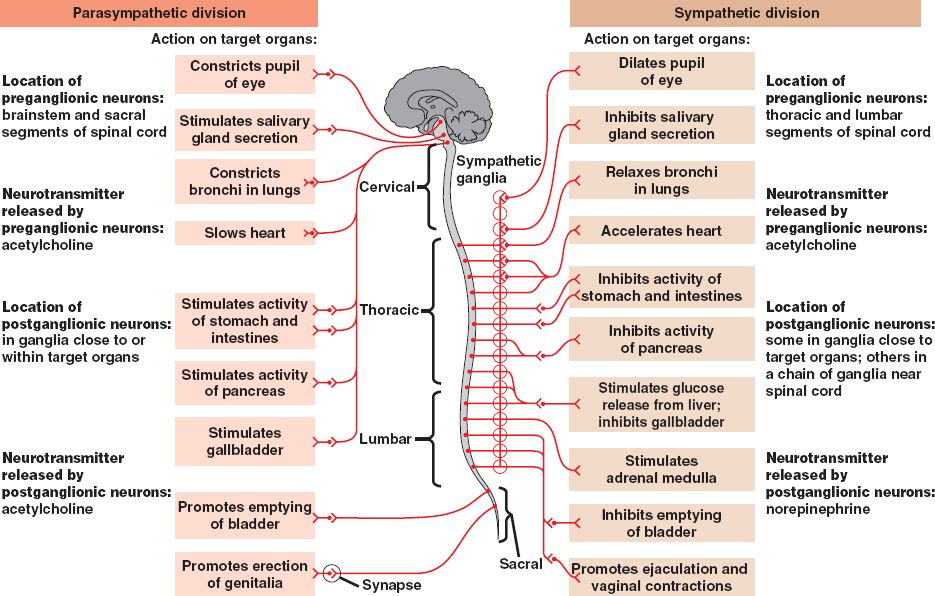

48_22ANSorganization

autonomic.html